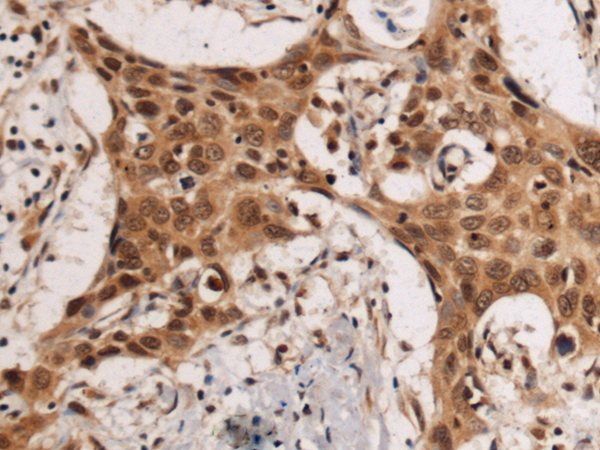

IHC positive control: |

Human esophagus cancer |

IHC Recommend dilution: |

50-200 |